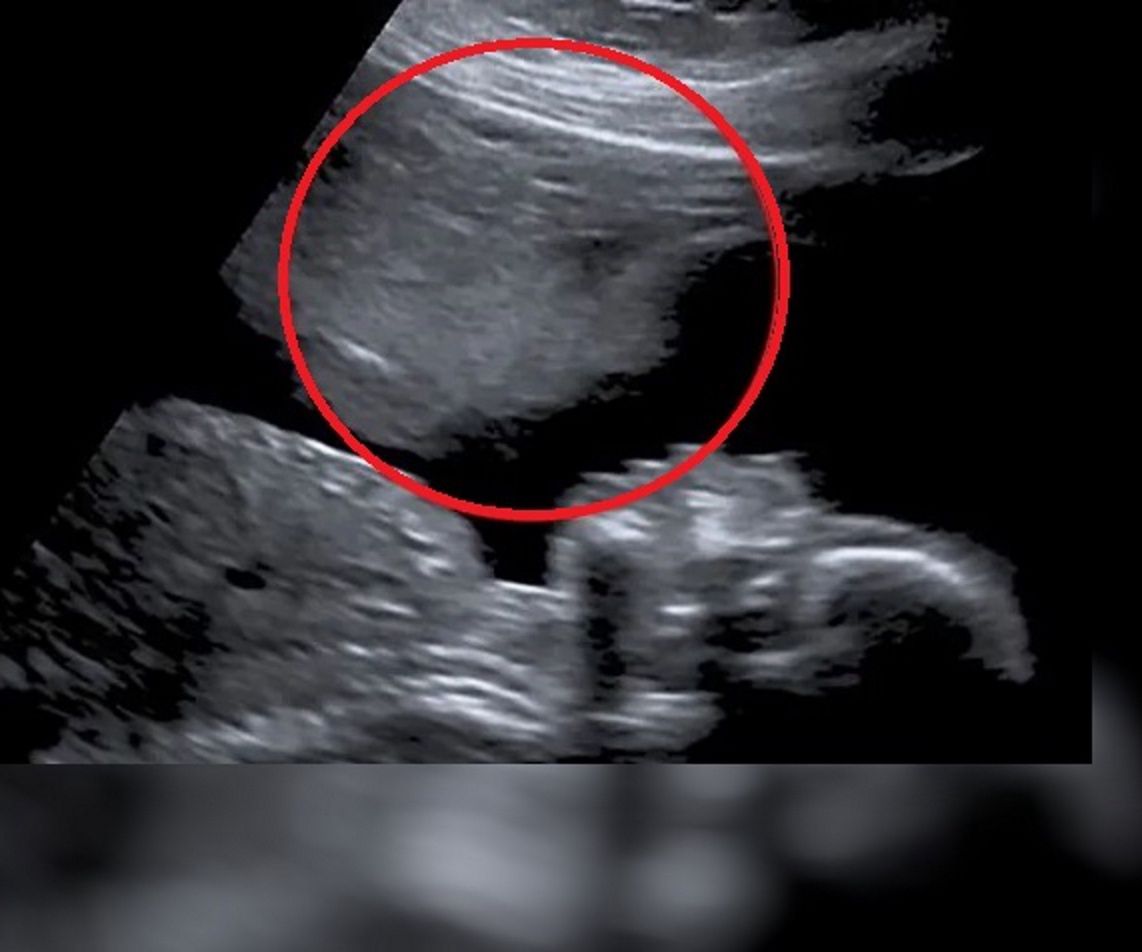

Stacey Astley z Taunton w południowo-zachodniej Anglii, bardzo pragnęła zostać mamą. Niestety wskutek komplikacji poroniła trzy kolejne ciąże. Ostatnie poronienie było dla niej tak wielkim przeżyciem, że postanowiła pogodzić się z losem i przestać starać się o dziecko.

Zaledwie po pięciu tygodniach okazało się, że kobieta jest w następnej ciąży. Jednak zaledwie tydzień po pierwszym badaniu kobieta zaczęła krwawić i okazało się, że ma potężnego krwiaka, tuż obok zarodka. Stacey była przekonana, że dojdzie do kolejnego poronienia.

Tak się jednak nie stało, kolejne badania wykazywały, że dziecko jest zdrowe, krwiak zaś zmniejszył się o połowę. Jednak największe wrażenie zrobiło na kobiecie badanie USG w 20. tygodniu ciąży.

Na ekranie ultrasonografu, tuż nad twarzą jej dziecka, pojawiła się druga, która nieco przypominała ducha. Według Stacey był to "anioł stróż", który chronił dziecko przed komplikacjami.

Kobieta urodziła zdrowego chłopca i bardzo mocno wierzy, że ich "anioł stróż" odegrał w tym wszystkim znaczącą rolę.